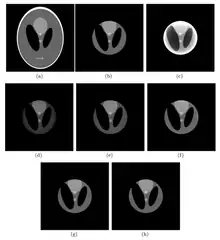

The first interior-reconstruction method listed below is extrapolation. It is a local tomography method which eliminates truncation artifacts but introduces another type of artifact: a bowl effect. An improvement is known as the adaptive extrapolation method, although the iterative extrapolation method below also improves reconstruction results. In some cases, the exact reconstruction can be found for the interior reconstruction. The local inverse method below modifies the local tomography method, and may improve the reconstruction result of the local tomography; the iterative reconstruction method can be applied to interior reconstruction. Among the above methods, extrapolation is often applied.

Comparison of methods

The extrapolation method is suitable in a situation where

- and

- i.e. a small truncation artifacts situation.

The adaptive extrapolation method is suitable for a situation where

- i.e. a normal truncation artifacts situation. This method also offers a rough solution for the exterior region.

The iterative extrapolation method is suitable for a situation in which

- i.e. a normal truncation artifacts situation. Although this method gets better interior reconstruction compared to adaptive reconstruction, it misses the result in the exterior region.

Local tomography is suitable for a situation in which

- i.e. a largest truncation artifacts situation. Although there are no truncation artifacts in this method, there is a fixed error (independent of the value of ) in the reconstruction.

The local inverse method, identical to local tomography, suitable in a situation in which

- i.e. a largest truncation artifacts situation. Although there are no truncation artifacts for this method, there is a fixed error (independent of the value of ) in the reconstruction which may be smaller than with local tomography.

The iterative reconstruction method obtains a good result with large calculations. Although the analytic method achieves an exact result, it is only functional in some situations. The fast extrapolation method can get the same results as the other extrapolation methods, and can be applied to the above interior reconstruction methods to reduce the calculation.